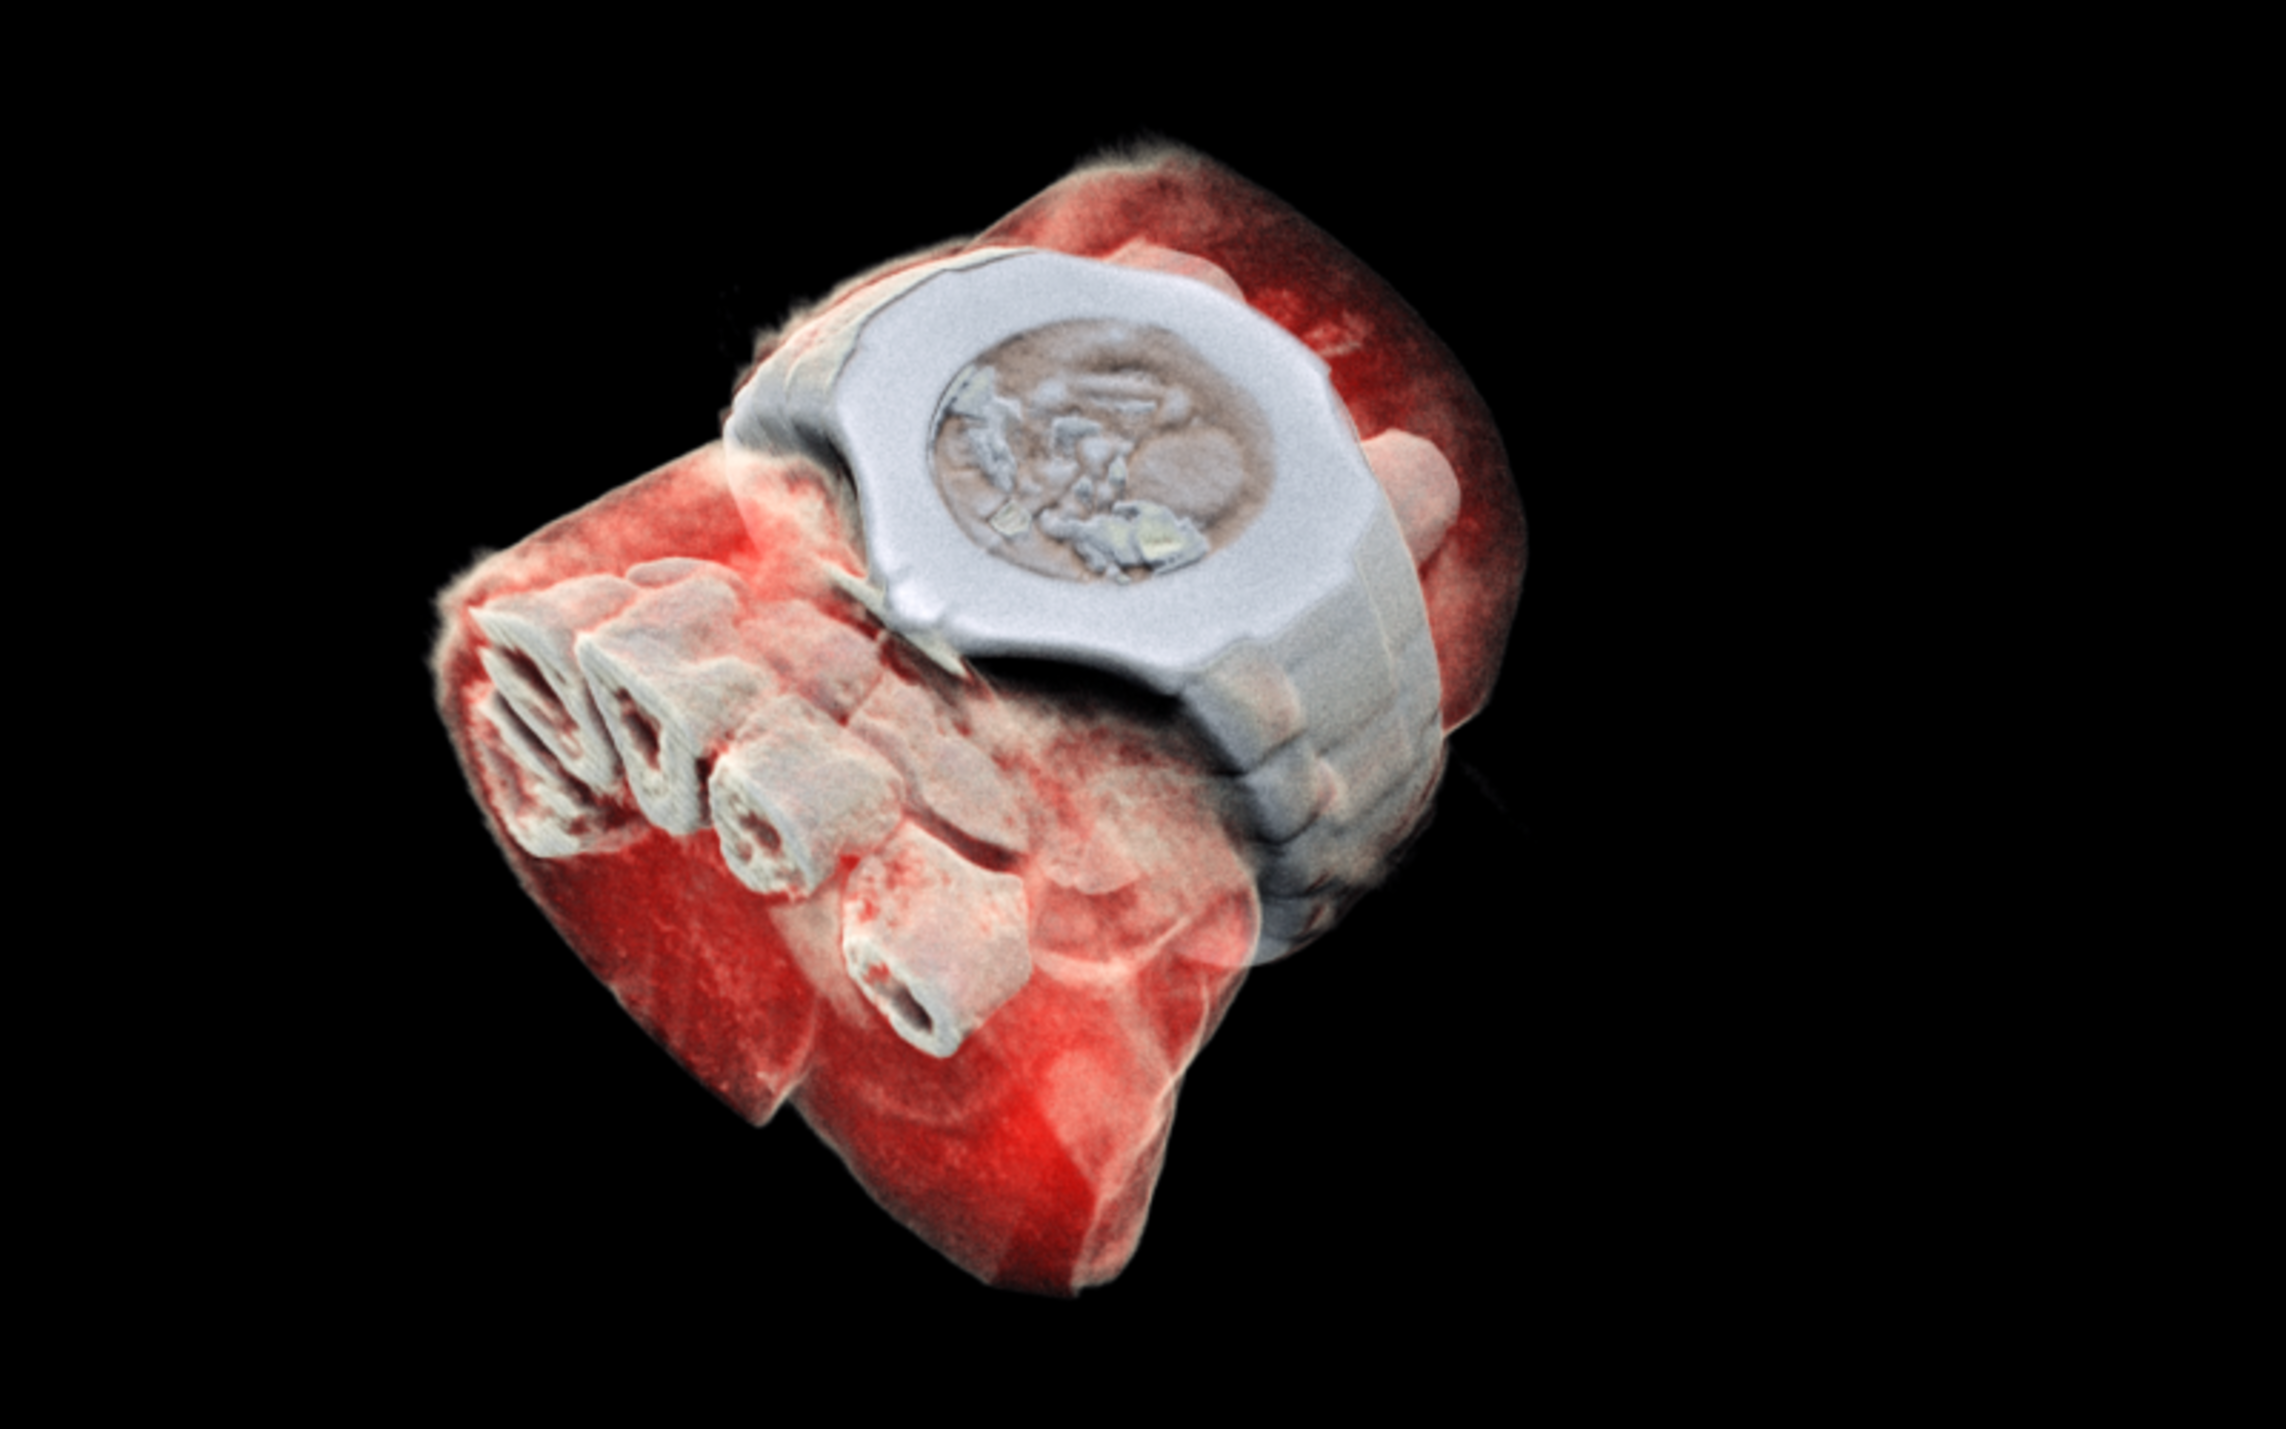

What if, instead of a black and white X-ray picture, a doctor of a cancer patient had access to colour images identifying the tissues being scanned? This colour X-ray imaging technique could produce clearer and more accurate pictures and help doctors give their patients more accurate diagnoses.

MARS’ solution couples the spectroscopic information generated by the Medipix3 enabled detector with powerful algorithms to generate 3D images. The colours represent different energy levels of the X-ray photons as recorded by the detector and hence identifying different components of body parts such as fat, water, calcium, and disease markers.